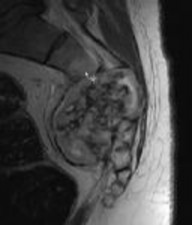

Figures 1 through 3 show sagittal and axial MRIs and a radiograph from a

77-year-old woman with leg pain when standing and walking of 1 year duration. The pain improves when she leans forward. She has been in physical therapy, taken oral analgesics, and had epidural injections with minimal relief. What is the best next step?

4. Microdiskectomy Discussion: B

The patient has lumbar stenosis of L2-3 and L3-4. She has no spondylolisthesis or instability. For her condition, spinal fusion plays a minimal role. She has no evidence of instability, and her condition can be addressed through laminectomy only. No role exists for microdiskectomy, because her disease results from a combination of ligamentum flavum hypertrophy and facet hypertrophy.